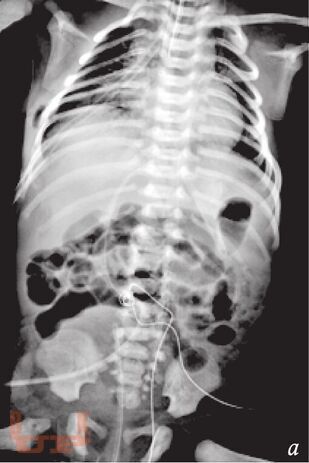

В методическом пособии описаны наиболее распространенные аномалии и пороки развития пищеварительного тракта у детей, а также лучевые методы исследования, с помощью которых диагностируют такие аномалии и пороки.

Пособие иллюстрировано фотографиями оригинальных рентгенограмм и схемами, облегчающими понимание изложенной темы.